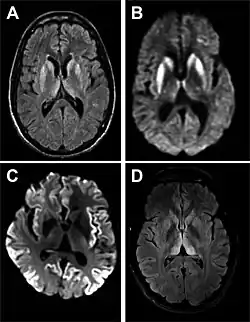

MRI of iCJD because of growth hormone

The defective protein can be transmitted by contaminated harvested human brain products, corneal grafts,[28] dural grafts,[29] or electrode[30] implants and pituitary human growth hormone, which has been replaced by recombinant human growth hormone that poses no such risk.[31]

• MRI with diffusion weighted inversion (DWI) and fluid-attenuated inversion recovery (FLAIR) shows a high signal intensity in certain parts of the cortex (a cortical ribboning appearance), the basal ganglia, and the thalami.[42] The most common presenting patterns are simultaneous involvement of the cortex and striatum (60% of cases), cortical involvement without the striatum (30%), thalamus (21%), cerebellum (8%) and striatum without cortical involvement (7%). In populations with a rapidly progressive dementia (early in the disease process), MRI has a sensitivity of 91% and specificity of 97% for diagnosing CJD.[46] The MRI changes characteristic of CJD may also be seen in the immediate aftermath (hours after the event) of autoimmune encephalitis or focal seizures.[42]

Imaging of the brain may be performed during medical evaluation, both to rule out other causes and to obtain supportive evidence for diagnosis. Imaging findings are variable in their appearance and also variable in sensitivity and specificity.[49] While imaging plays a lesser role in diagnosis of CJD,[50] characteristic findings on brain MRI in some cases may precede onset of clinical manifestations.[51]

Brain MRI is the most useful imaging modality for changes related to CJD. Of the MRI sequences, diffuse-weighted imaging sequences are most sensitive.[52] Characteristic findings are as follows:

• Focal or diffuse diffusion-restriction involving the cerebral cortex or basal ganglia. The most characteristic and striking cortical abnormality has been called "cortical ribboning" or "cortical ribbon sign" due to hyperintensities resembling ribbons appearing in the cortex on MRI.[53] The involvement of the thalamus can be found in sCJD, is even stronger and constant in vCJD.[54]

• Varying degree of symmetric T2 hyperintense signal changes in the basal ganglia (i.e., caudate and putamen), and to a lesser extent globus pallidus and occipital cortex.[50]

Brain FDG PET-CT tends to be markedly abnormal, and is increasingly used in the investigation of dementias.

• Patients with CJD will normally have hypometabolism on FDG PET.[55]